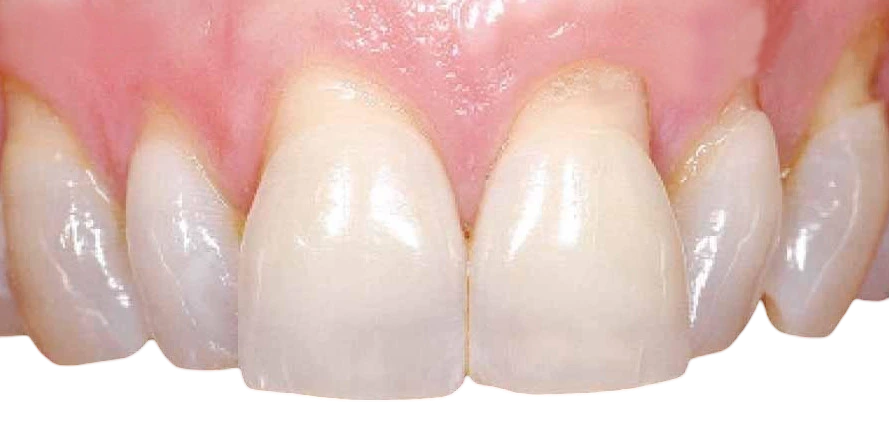

Encias retraidas antes y despues

Injerto de encías: la solución definitiva

Es uno de los tratamientos más efectivos cuando la pérdida de tejido es importante. Consiste en tomar una pequeña muestra de encía del propio paciente (normalmente del paladar) y colocarla en la zona afectada.

Beneficios del injerto:

- Cubre la raíz expuesta completamente.

- Protege el diente de futuras caries.

- Mejora la estética de la sonrisa.

- Reduce la sensibilidad dental.